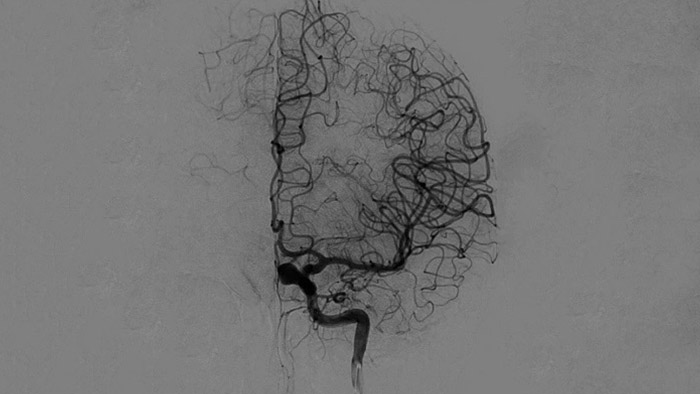

Scharfe Bilder dank 2D DSA mit ClarityIQ

2D DSA mit ClarityIQ

Die automatische Bewegungskompensation von ClarityIQ ermöglicht auch während Echtzeit-DSA scharfe Bilder der Gefäße und unterstützt so die sichere Entscheidungsfindung während Schlaganfallbehandlungen.

Verifizierung des Behandlungserfolgs

DSA Visualisierung

Hochwertige DSA-Visualisierungen ermöglichen es Ihnen, zu beurteilen, ob das Gerinnsel vollständig entfernt wurde und ob sich Teile davon distal in das Gehirn verteilt haben. Sie können die Wiederherstellung des Blutflusses zur Penumbra verifizieren und eine Überprüfung auf periprozedurale Blutungen vornehmen.